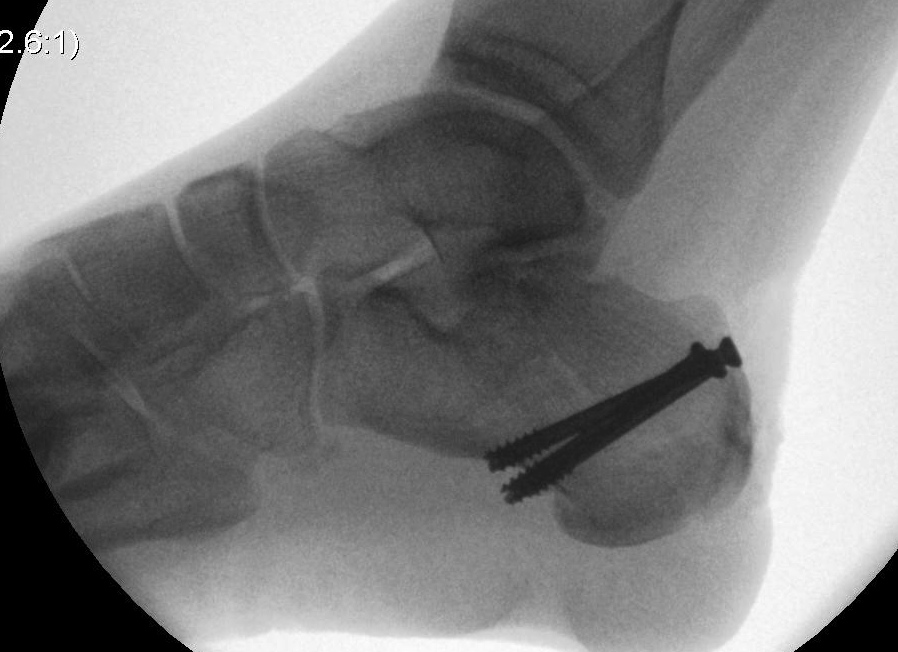

ORIF lateral plate using extensile lateral approach

Depuy Synthes calcaneal locking plates PDF

Technique

AO surgery reference extensile lateral approach

AO surgery calcaneal ORIF lateral plate

Vumedi ORIF calcaneum via extensile lateral approach

Position

- patient on side, blankets under foot

- operated foot up

- radiolucent table, image intensifier

Extensile lateral approach

- vertical limb: between tendoachilles and fibula

- horizontal limb: in line with 5th metatarsal towards CC joint

- full thickness flaps - care ++++ with apex of incision

- divide peroneal retinaculum

- peroneal tendons elevated

K wires to retract skin flap

- 2 in talus / 1 in fibula

Expose subtalar joint

Reduction of varus

- Steinmann pin into tuberosity

- can elevate and pull out of varus

Reduction of subtalar joint

- open lateral wall fragment to access to subtalar joint

- lamina spreader

- reduce and ORIF with screws

- reduce and ORIF sustentaculum fragment

Anatomical contoured locking plate